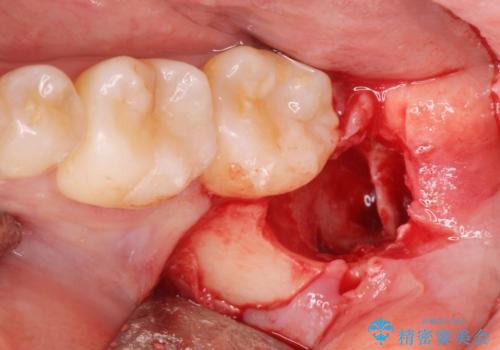

- 左下親知らずが腫れてる感じがして痛いとの事で来院。

抜歯を希望されたので抜歯術を行いました。

- 外科手術のため、術後に出血、痛みや腫れ、違和感を伴います